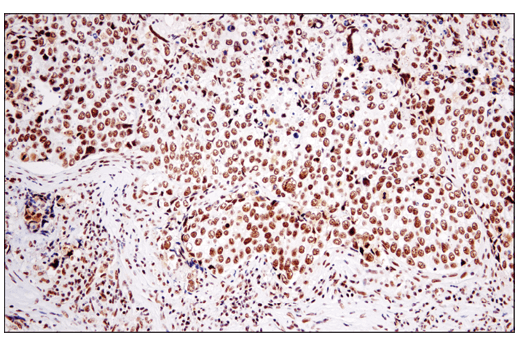

Immunohistochemical analysis of paraffin-embedded human ductal breast carcinoma using DNA-PKcs (E6U3A) Rabbit mAb.

undefined Image 4: PhosphoPlus<sup>®</sup> DNA-PKcs (Ser2056) Antibody Duet

Immunohistochemical analysis of paraffin-embedded human ductal breast carcinoma using Phospho-DNA-PKcs (Ser2056) (E9J4G) Rabbit mAb.

undefined Image 5: PhosphoPlus<sup>®</sup> DNA-PKcs (Ser2056) Antibody Duet